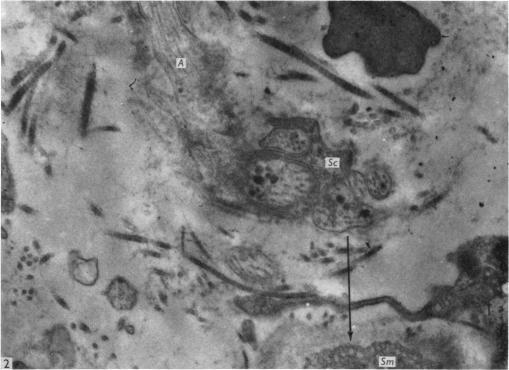

Fine structural study of the terminal effecror plexus, neuromuscular and intermuscular relationships in the pulmonary artery.

J Anat. 1968 Jun;103(Pt 1):49-63.

PMID:5691966

原文链接:https://pmc.ncbi.nlm.nih.gov/articles/PMC1231874/